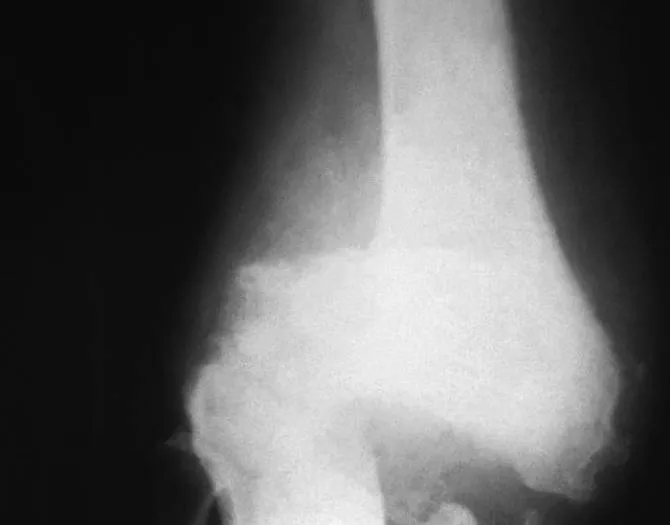

El deterioro óseo, por osteoporosis o por otras causas, es un problema médico muy común.

La labor de mantenimiento de nuestra estructura ósea se realiza esencialmente a través de dos tipos de células. Por un lado, están los osteoclastos, que degradan y reabsorben materia ósea. Por otro, están los osteoblastos, células constructoras de hueso.

Una forma simplificada de explicar sus tareas con un símil de la albañilería sería que las primeras realizan tareas de demolición de estructuras en demasiado mal estado y las segundas las reconstruyen en los espacios que han quedado vacíos y a punto para ello. Bajo condiciones normales, osteoclastos y osteoblastos trabajan juntos de manera bien coordinada, con las acciones de unos complementando las de los otros, y el resultado de esa labor conjunta sirve para mantener la salud de los huesos.

Ambos tipos de procesos son afectados por nuestros ritmos circadianos, ya que dependiendo de la hora del ciclo día-noche o vigilia-sueño, una clase de células tiende a estar más activa que la otra. El deterioro de la calidad del sueño que bastante gente experimenta al envejecer acaba provocando que los osteoclastos acostumbren a estar más activos de lo normal.